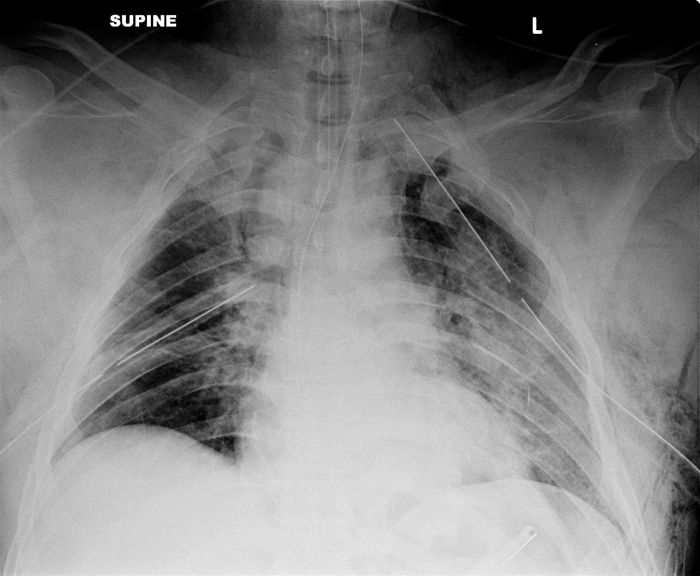

Hemothorax

Hemothorax, an accumulation of blood outside the visceral lung pleura, is a differential diagnosis of decreased breath sounds along with pneumothorax. However, it is differentiated by the presence of dullness to percussion on physical exam.

The management of hemothorax is often non-emergent, as parenchymal lung bleeding is often self-limiting. Initial management is a chest tube (tube thoracostomy).

Either a massive immediate drainage (greater than 1.5 L) or large ongoing drainage of the chest tube (200 to 300 ml per hour) warrants surgical intervention with thoracotomy to ligate the vessel. Bleeding in this manner is known to be thoracic (e.g. intercostal artery), as opposed to pulmonary parenchymal.